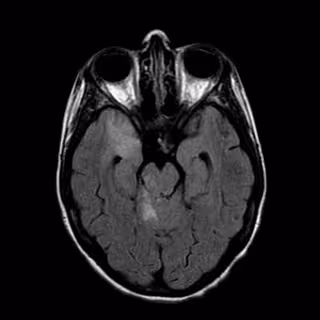

Pruebas a un paciente con ictus

"Un ictus es un trastorno brusco en la circulación sanguínea del cerebro que puede ser producido por oclusión arterial (el 85% de los casos) o por hemorragia (el 15%)", explica la doctora María Alonso de Leciñana, coordinadora del Grupo de Estudio de Enfermedades Cerebrovasculares de la Sociedad Española de Neurología.